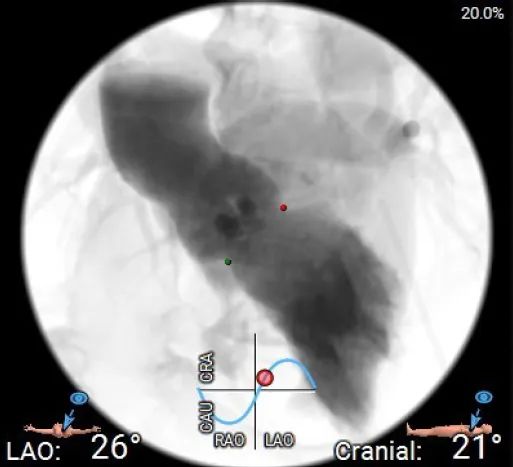

主动脉根部造影

释放体位

LAO体位

考虑到0型二叶瓣限制区域明显增加对于瓣膜释放的影响,在美敦力TAVR Best Practice释放原则下,推荐LR共窦使用cusp overlap角度,一般情况下0型二叶瓣可使用短径角度,此案例使用了模拟LR cusp overlap的体位,以评估0型二叶瓣TAVR的传导系统影响。